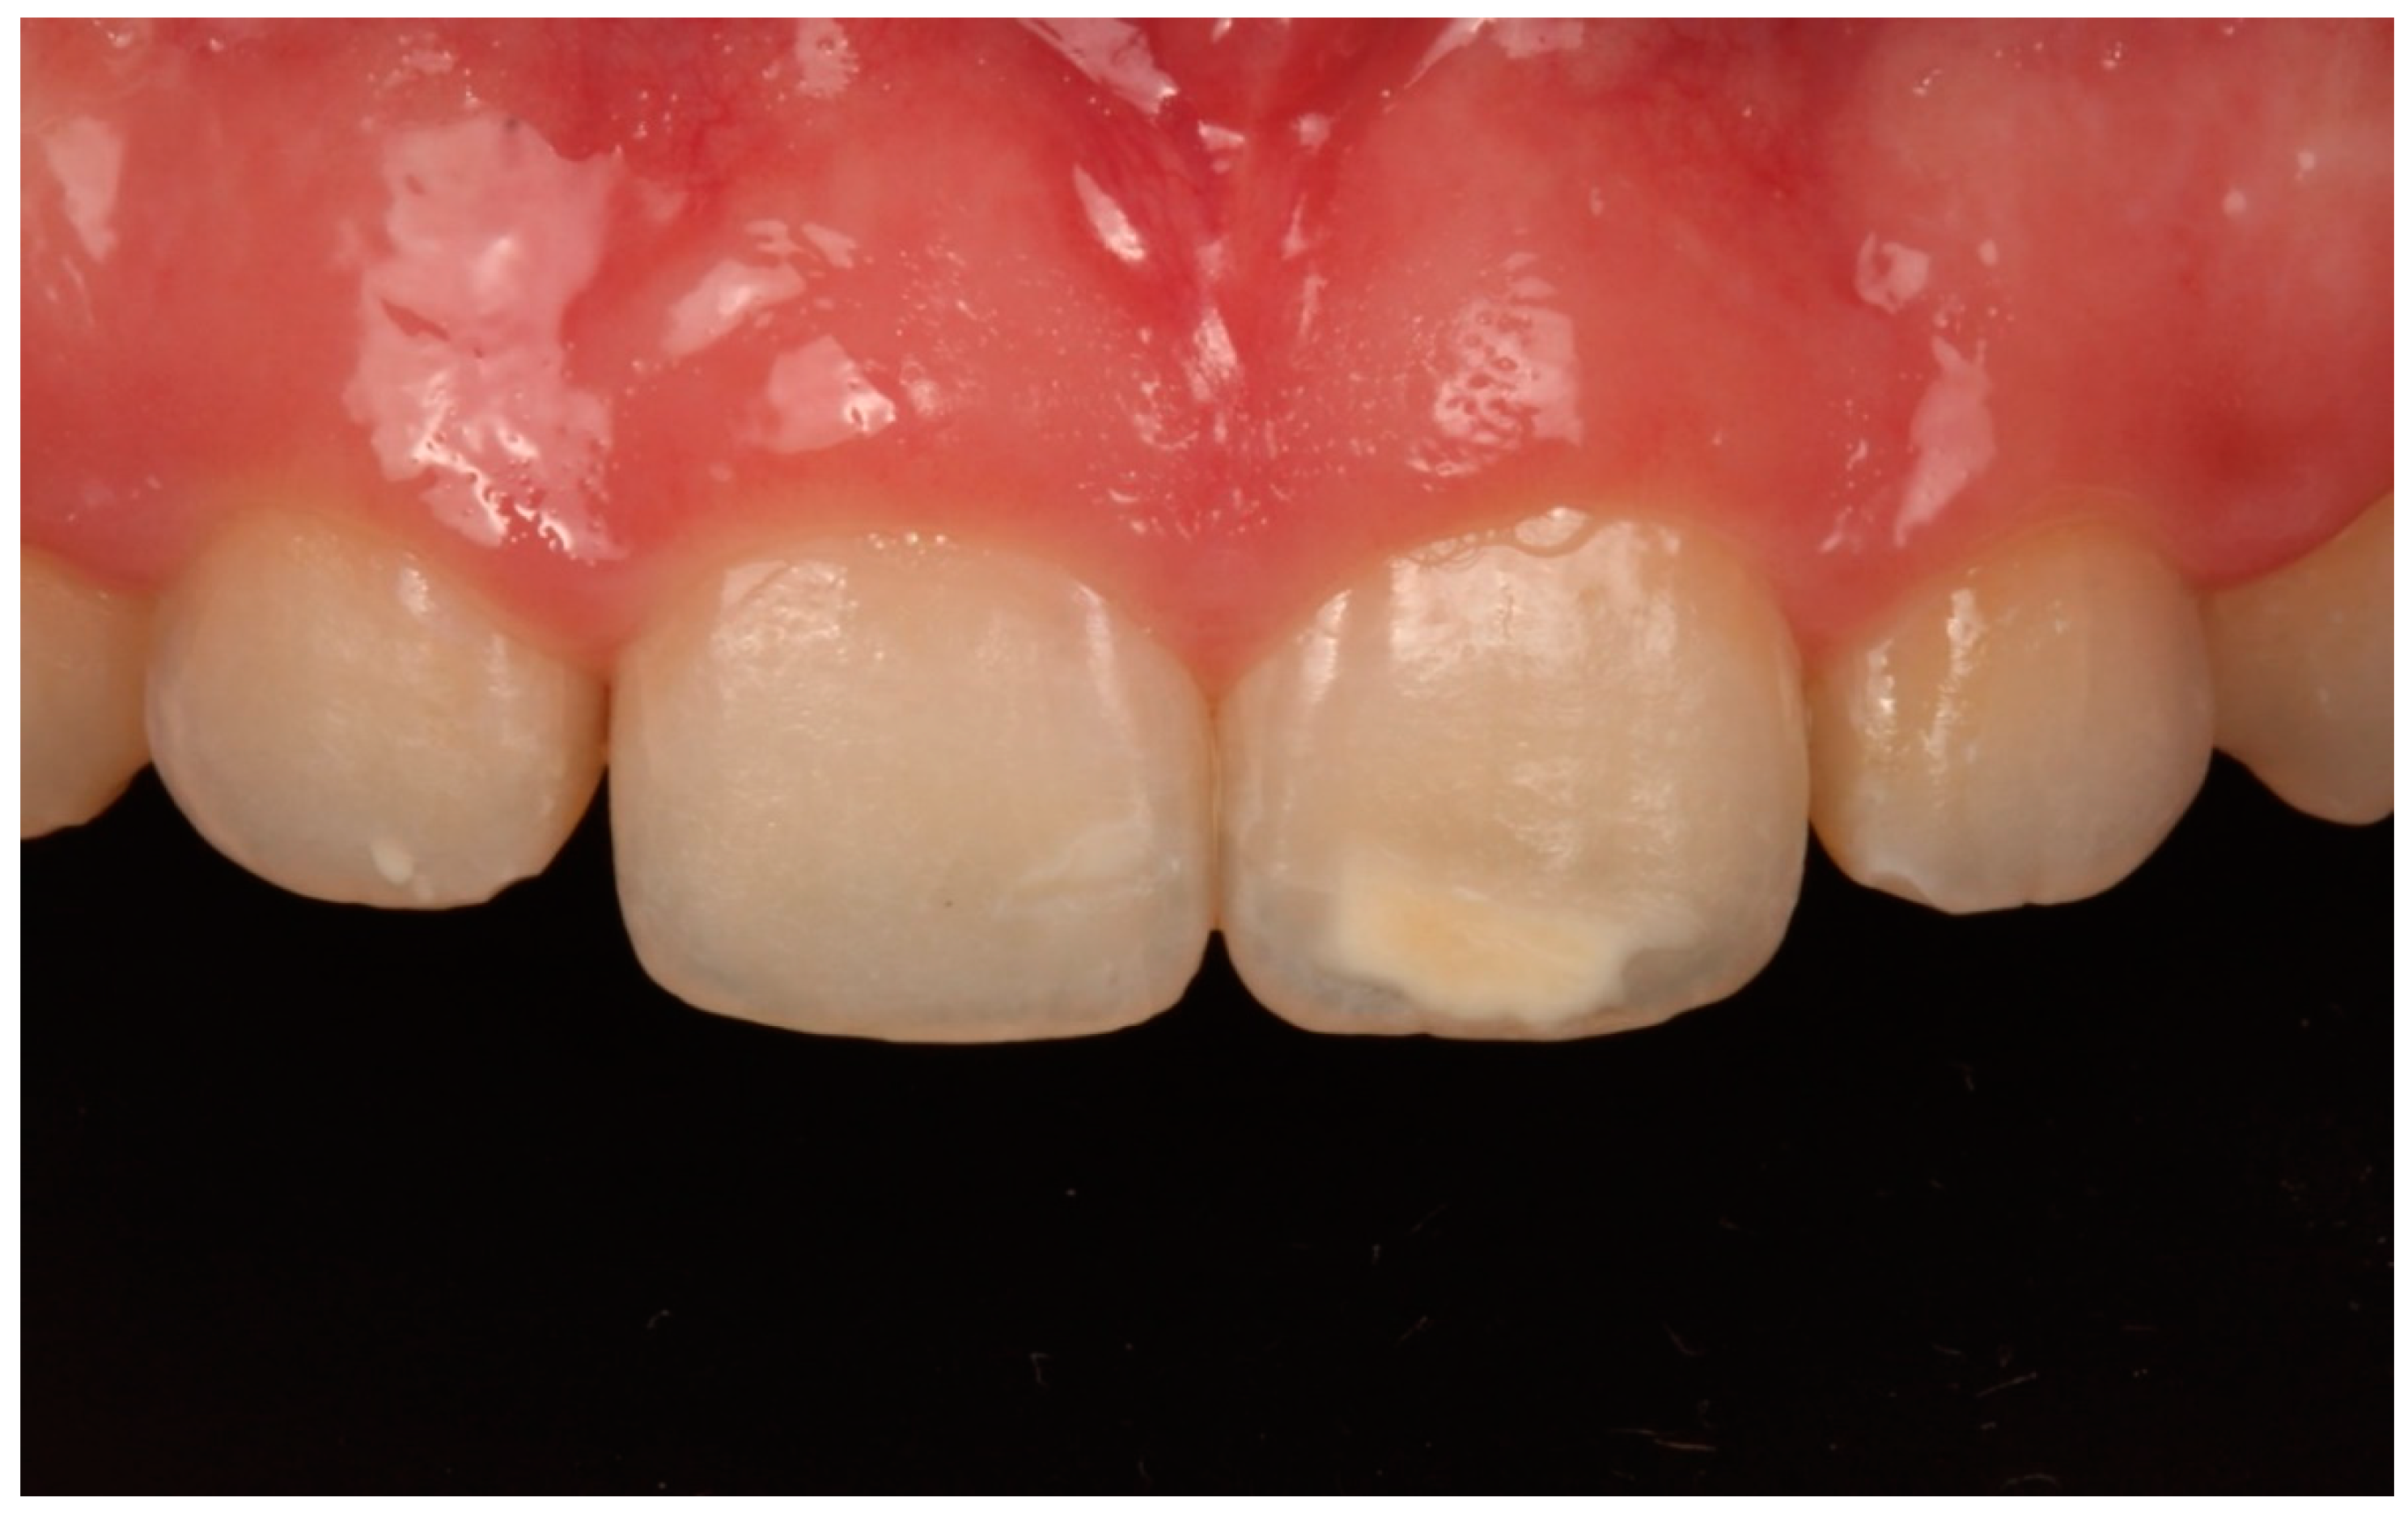

- In this study, the abrasive erosion treatment (Opalustre; Ultradent) contained a 6.6% HCl slurry with silicon carbide microparticles; this combination offered a chemical stain removal along with gentle mechanical abrasion. In cases using 6.6% HCl, teeth with white spots were treated with various applications according to the manufacturer’s instructions. The product was spread on the enamel surface in a 1 mm thick uniform layer. Afterwards, it was rubbed homogeneously for 1 min using Opal Cups (Ultradent) provided by the manufacturer. The enamel was then washed in abundant water for 30 s (Figure 4, Figure 5 and Figure 6).